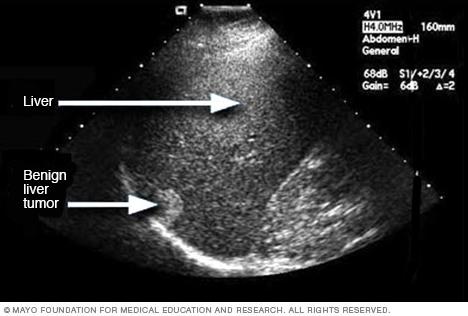

Ultrasound image of a liver tumor

An ultrasound uses sound waves to create an image. This ultrasound shows a noncancerous liver tumor.

• Imaging tests. An ultrasound, CT scan and MRI can show liver damage.